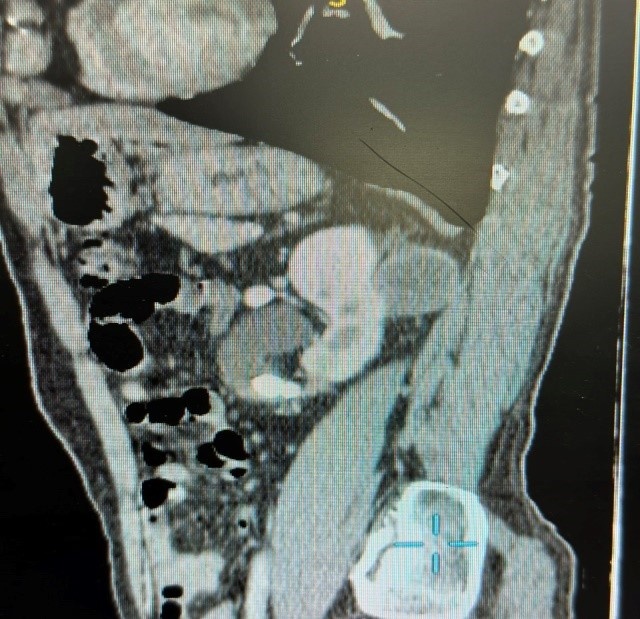

Người đàn ông cho hay đã được thực hiện nội soi niệu quản trái tán sỏi 3 năm. Tại bệnh viện này, kết quả khám và xét nghiệm cận lâm sàng cho thấy bệnh nhân rung thận trái, ấn điểm đau niệu quản trái 1/3 trên. Hình ảnh CT scan hệ tiết niệu có nang thận trái (36x45 mm), thành dày không đều, ngấm thuốc sau tiêm, nang thận phải Bosniak I, sỏi niệu quản trái 1/3 trên gây giãn thận độ 2.

Các bác sĩ khoa Tiết niệu trên đã hội chẩn và đưa ra chẩn đoán nang thận trái Bosniak IV có nguy cơ ung thư hóa và sỏi niệu quản trái 1/3 trên gây giãn thận độ II. Bệnh nhân có chỉ định phẫu thuật cắt bán phần thận trái kèm nang và mổ lấy sỏi niệu quản trái kết hợp một thì.

Hình ảnh nang thận trái Bosniak IV và sỏi niệu quản trái 1/3 trên. Ảnh: BVCC.

TS.BS Kiều Đức Vinh, khoa Tiết niệu trên, cho biết bệnh nhân vừa có sỏi niệu quản vừa có nang thận Bosniak IV nguy cơ ung thư cao nên cần phẫu thuật mổ mở, đi đường chéo bên, vào bộ lộ thận và niệu quản trái 1/3 trên, tiến hành lấy sỏi trước. Sau đó, bác sĩ khống chế cuống mạch thận để cắt thận trái bán phần kèm nang và mỡ xung quanh. Thời gian mổ mất 90 phút, không phải truyền máu sau mổ. Kết quả giải phẫu bệnh phẩm là ung thư biểu mô tế bào sáng của thận độ 1.